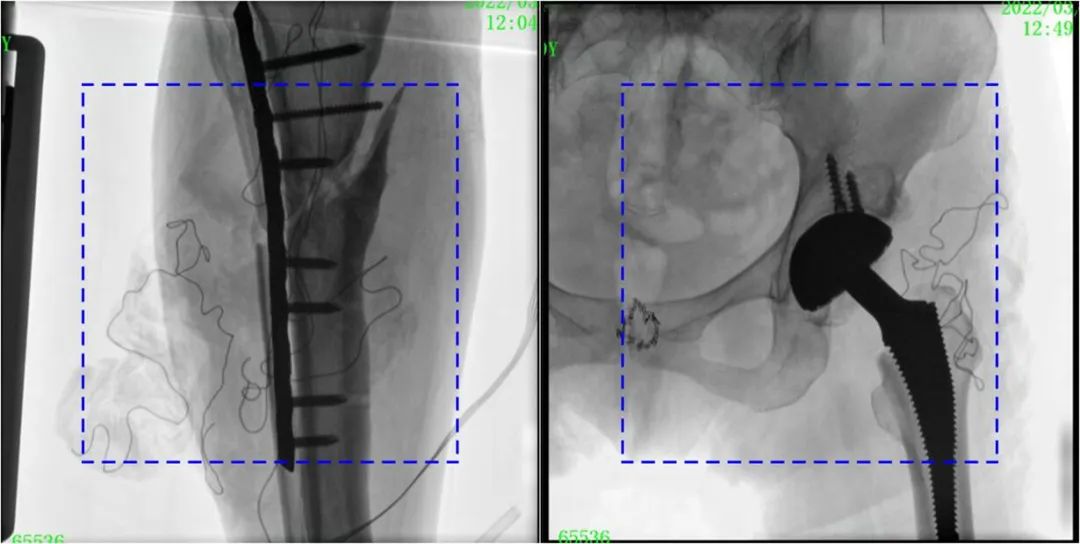

在進(jìn)行髓內(nèi)釘內(nèi)固定術(shù)時(shí),醫(yī)生需要同時(shí)觀察到入釘點(diǎn)和骨折部位的情況,普愛(ài)醫(yī)療大平板一體式C形臂采用30CM×30CM的平板探測(cè)器,能夠呈現(xiàn)更廣闊的成像面積,滿足大部分長(zhǎng)骨髓內(nèi)釘內(nèi)固定術(shù)的攝片需求。

PLX119C臨床圖像與傳統(tǒng)圖像對(duì)比

注:藍(lán)色虛線內(nèi)為傳統(tǒng)21CM×21CM平板的成像區(qū)域。